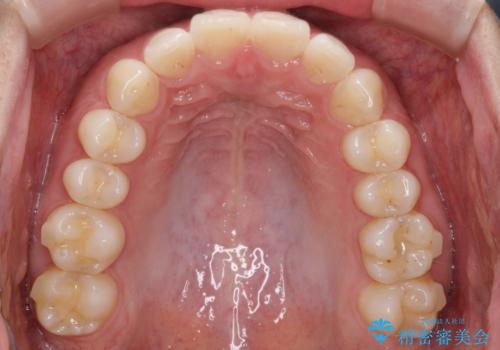

【前歯のガタガタが気になる】インビザライン症例

- 前歯の歯並びの改善を希望され来院された患者様です。

初診時の歯並びの状態としては、下顎前歯に及ぶの中等度のがたつき(叢生)があり、前歯が深く噛みこんでいる状態でした。

抜歯は行わず歯列弓の拡大やディスキング(歯と歯の間の隙間を作る処置)を行い叢生を改善しました。

矯正装置としてはマウスピースを使用しています。

見た目、嚙み合わせ及び、治療期間や施術内容に大変ご満足いただきました。